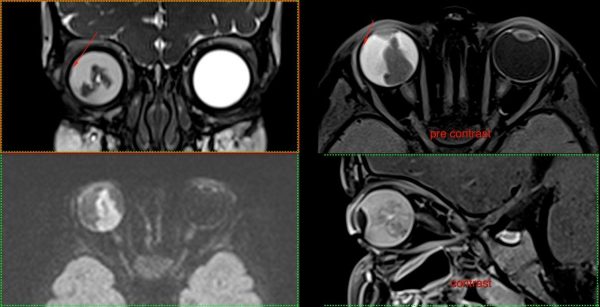

- МРТ: Створює найчіткіші зображення м’яких тканин, органів та судин. Без використання шкідливого випромінювання, тому також підходить для візуалізації вагітних, дослідженні плоду.

У нас є можливість проведення досліджень високої роздільної здатності всіх органів та систем (за винятком серця), зокрема в складі синдромів/комбінованих вадах. Обстеження виконуються, як для дітей так і дорослих пацієнтів, в т.ч. з анестезіологічним забезпеченням (седація, наркоз).

Магнітно-резонансна томографія: Найточніший метод для дослідження мозку, хребта, суглобів та м’яких тканин. Абсолютно безпечний тому також підходить для візуалізації вагітних, дослідженні плоду. Разом КТ та МРТ показані для виявлення вроджених аномалій розвитку/патології центральної нервової, скелетно-м’язової, травної, дихальної, сечовидільної системи, статевої сфери Також показані пацієнтам та потенційним донорам при підготовці до трансплантації,

- Магнітно-резонансна томографія: Siemens MAGNETOM Aera (1,5 Тл)